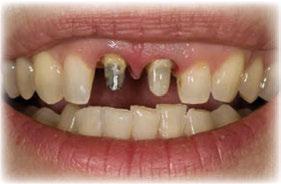

Figuras 4 y 5. Imagen intraoral y de sonrisa de la paciente en la primera visita. En ellas observamos el colapso de la mordida a nivel anterior, con una sobremordida del 100%.

Figuras 6 y 7. Al retirar las prótesis removibles observamos en el arco inferior una gran reabsorción ósea del sector posterior, con elevación del suelo de la boca y la invasión de los tejidos blandos, lo que nos hace suponer que existe una gran atrofia ósea asociada.

Figuras 18-21. Imágenes iniciales y finales de la paciente a los dos años de seguimiento donde observamos el cambio de la sonrisa y la recuperación de la dimensión vertical realizada con la rehabilitación sobre implantes y la confección de nuevas prótesis sobre implantes en el primer cuadrante y facetas en los sectores anteriores superiores e inferiores.